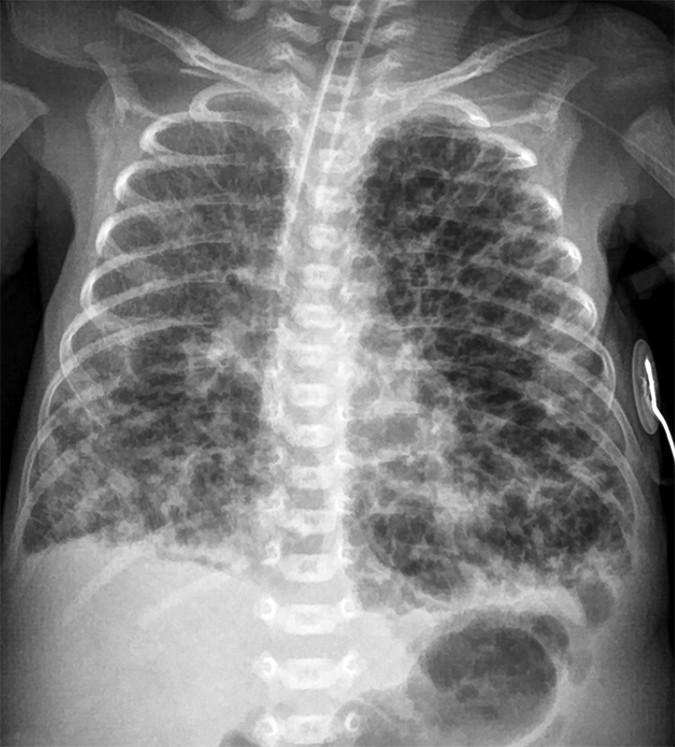

BPD (Bronchopulmonary Dysplasia) Hyperinflation; cystic lucencies; linear fibrotic stranding; heterogeneous opacification Chronic lung disease: oxygen requirement at 28+ days of life; sequela of prolonged ventilation and prematurity